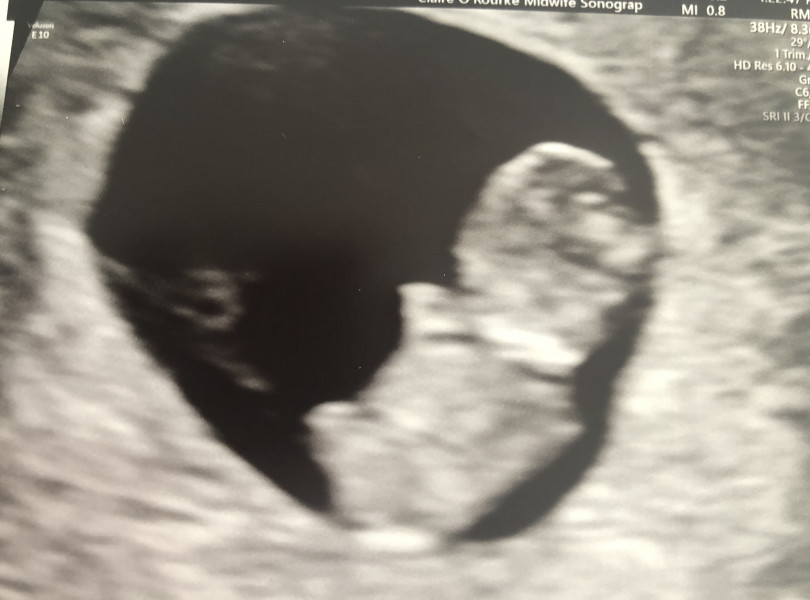

After more spotting on Sunday I was really, really nervous about my scan today, but it went great.

I was previously measuring 5 days behind my LMP dates and today I measured 4 days behind my LMP dates so all looking good and on track with a revised due date of 7 December 😁 It looks so much more like a baby than at my last scan 13 days ago, it was wiggling away too! I am over the moon!

LolaJ87 · 05/05/2022 15:32

Whoops, photo didn’t attach!

Its a photo of a hard copy, so not the best quality but it was super clear on the screen.

@LolaJ87 what fantastic news and a great pic!

@LolaJ87 that's a lovely picture! How many weeks are you? It's crazy how quickly they change!! Can't wait for my scan on 27th!

@lovesT I was 9+5 going by my LMP dates but I'm 9+1 based on measurements. They'll check again on the 23rd 😀

The only downside of measuring behind is that because I've just hit 9 weeks and I'm chunky, my NIPT may be inconclusive. So they did say there's a chance I'll need to come back for a re-draw.